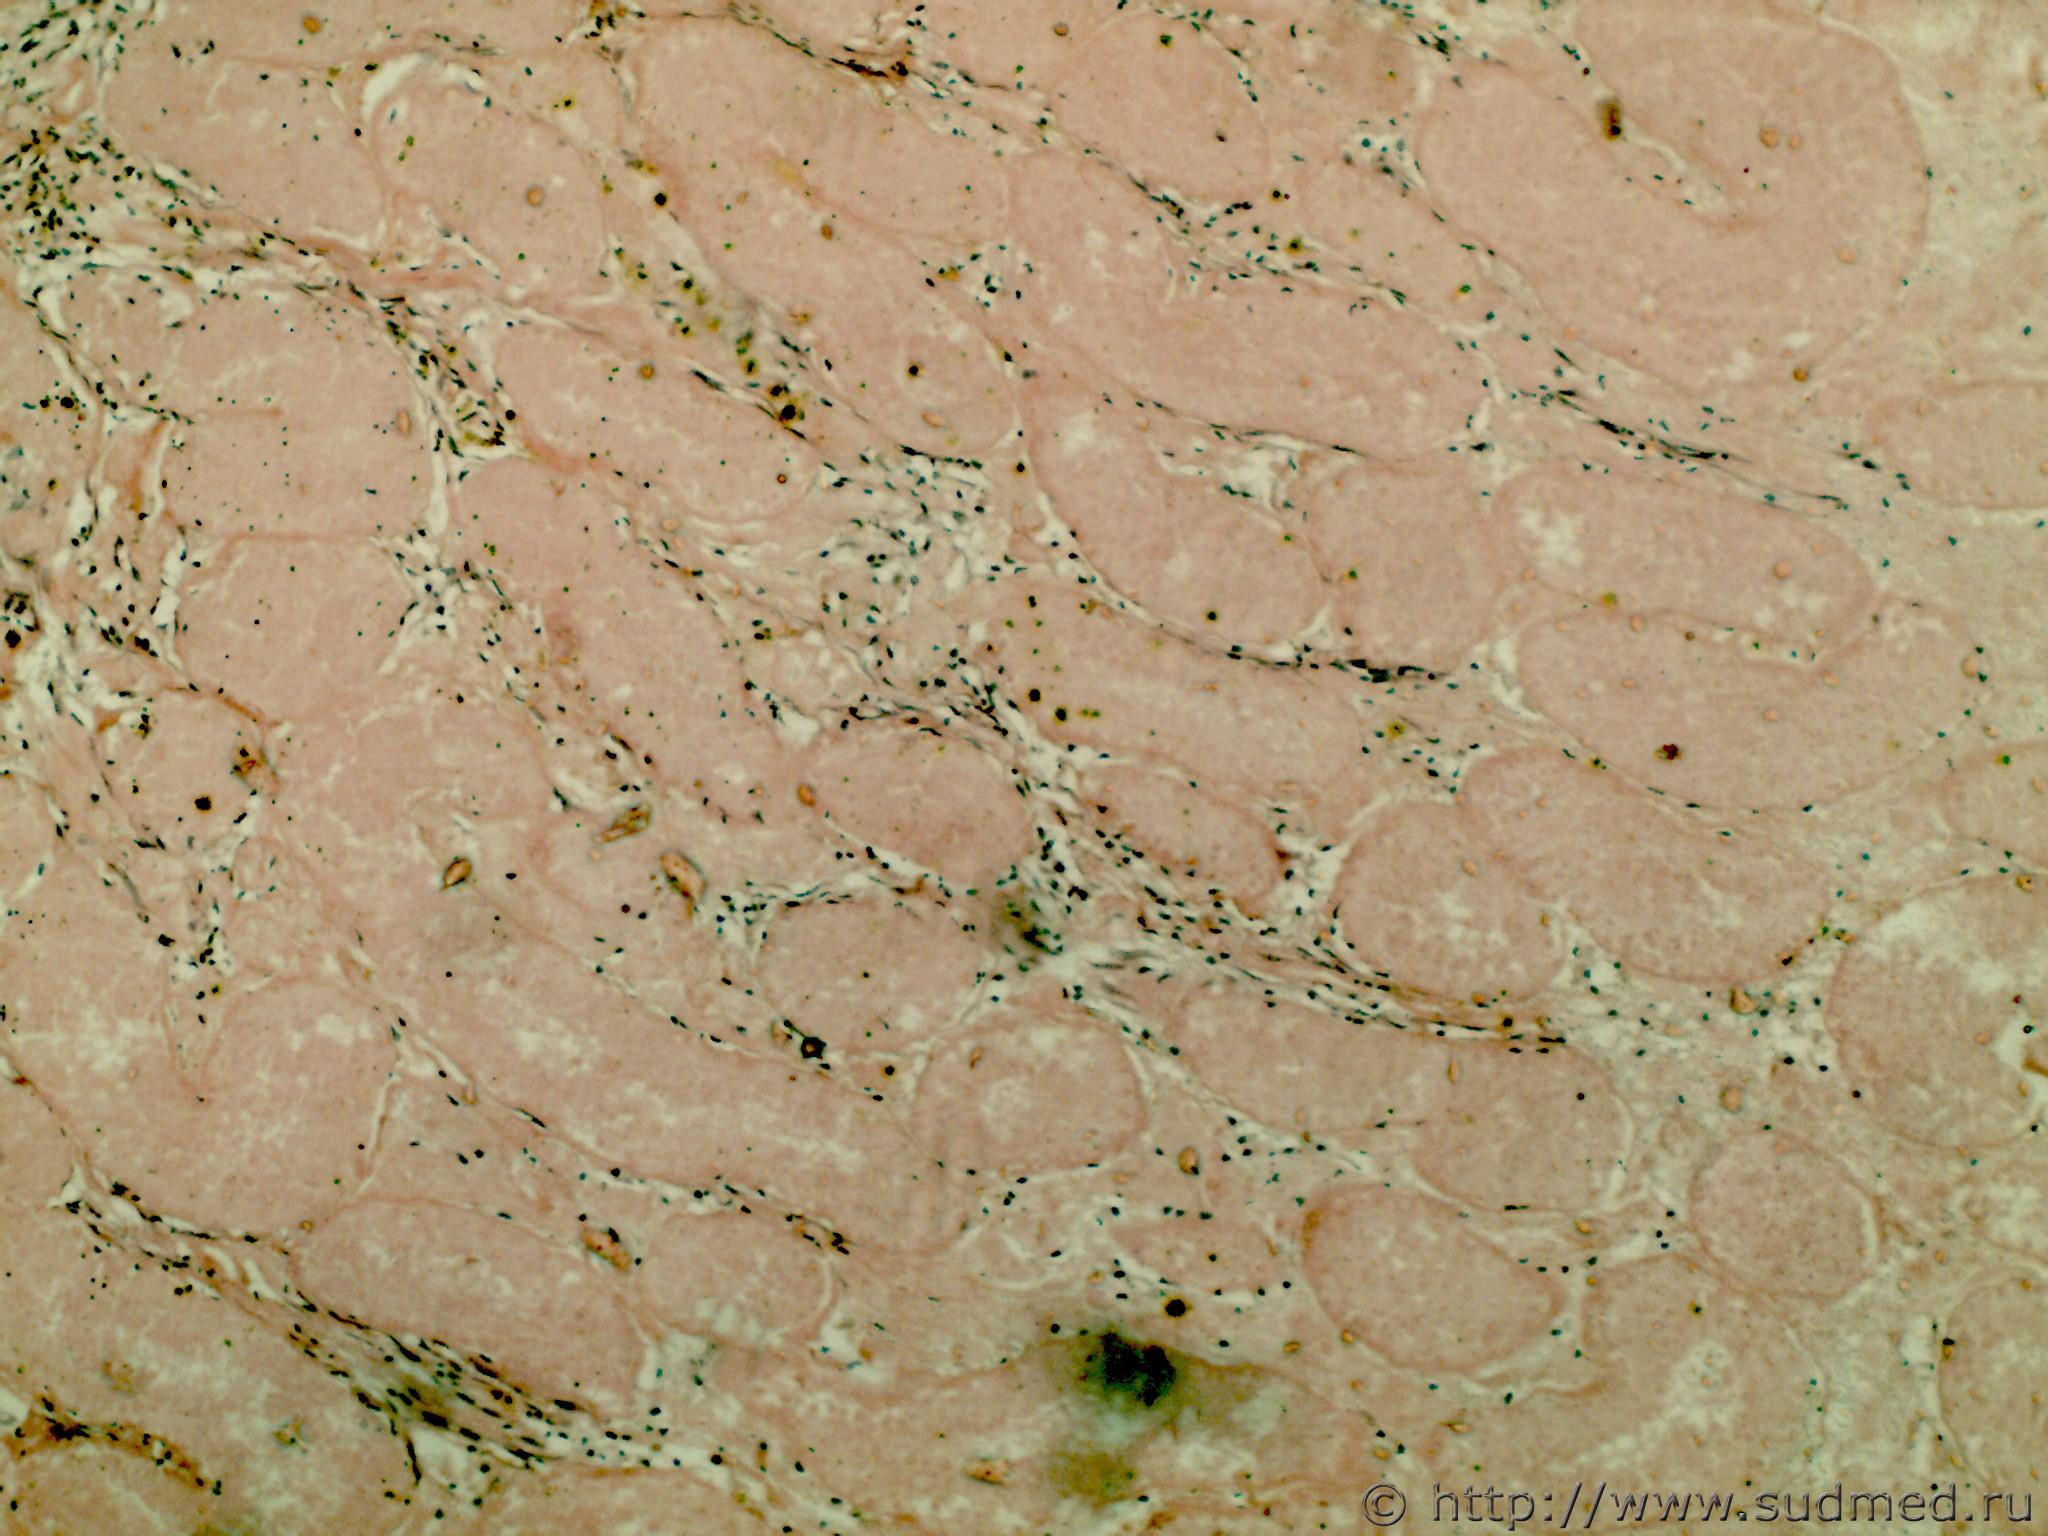

Ув. коллеги нужна помощь. У мальчика 15 лет появились резкие боли в правой половине мошонки. ДЗ: орхоэпидидимит справа. Данных за перекрут канатика нет. 1,5 мес. консервативного лечения и повторные УЗИ (некротически измененный придаток?) с выраженным его увеличением в объеме. Операция: высокая орфофуникулоэктомия справа по поводу перекрута и некроза правого яичка. Необходимо установить давность некроза яичка. 1-5 белочная оболочка и ткань яичкаСудебная медицина - Прикрепленное изображение Судебная медицина - Прикрепленное изображениеСудебная медицина - Прикрепленное изображениеСудебная медицина - Прикрепленное изображениеСудебная медицина - Прикрепленное изображение

остальные ткань яичка Судебная медицина - Прикрепленное изображение Судебная медицина - Прикрепленное изображениеСудебная медицина - Прикрепленное изображениеСудебная медицина - Прикрепленное изображениеСудебная медицина - Прикрепленное изображение

думаю, соответствует указанному сроку. Хотя не знаю, можно ли устанавливать сроки давности некроза, как таковой литературы нет, кроме методички Белянина "давность воспалительного процесса", в которой очень поверхностные и общие данные. В капсуле и ткани яичка грануляционная ткань, фибробласты, фиброциты, лимфо-гистиоцитарная инфильтрация, местами кровяной пигмент.

Литературные данные говорят, что при перекруте яичка страдает венозный отток, будет тромбоз и обширные кровоизлияния, геморрагический некроз паренхимы. В данном случае морфология некроза соответствует перекруту?